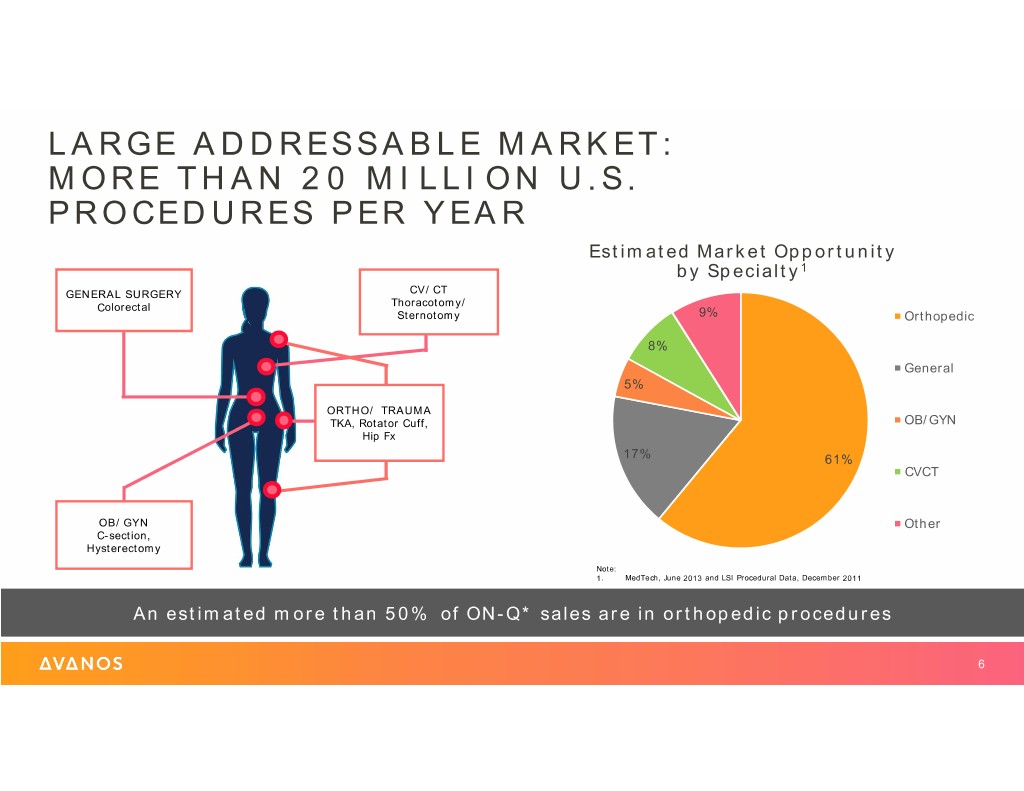

June2118analystandinve